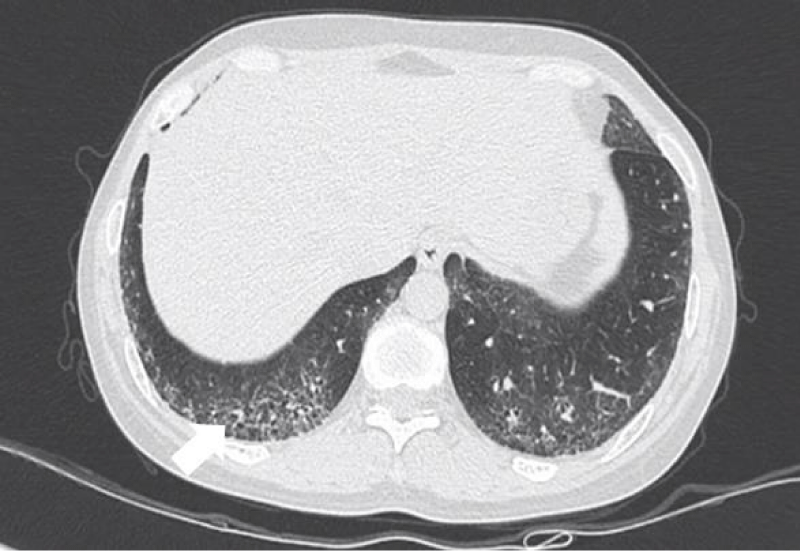

Figure 7: Different levels HRCT images from a 65 year-old male considered as NSIP pattern.

The most common pattern in SSc-ILD was NSIP, accounted for 71.6% (83 patients); secondly was UIP, accounted for 25.9%, and 3 patients presented consistent with LIP.

Histopathologically, NSIP was characterized by a uniform appearance of varying amounts of interstitial inflammation and fibrosis, and divided into cellular pattern (cNSIP) and fibrotic pattern (fNSIP). The typical finding of cNSIP was diffuse inflammatory cell infiltration without obvious fibrosis; fNSIP characterized by diffuse thickening of the alveolar walls with or without inflammatory cell infiltration [18]. On HRCT, cNSIP showed ground-glass opacities mainly, reticular opacities and traction bronchiectasis were relatively infrequent, without honeycombing; patients with fNSIP had few honeycombing, as well as greater extent of ground-glass opacities, traction bronchiectasis, and opacities than those with cNSIP [19].